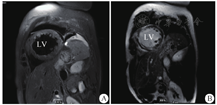

LV:左心室;A:T2压脂示室间隔及左室心肌多发斑片状水肿信号;B:延迟强化示弥漫多发延迟强化